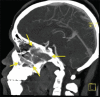

Juvenile nasopharyngeal angiofibroma (JNA) is a rare benign tumor arising predominantly in the nasopharynx of adolescent males. It is an aggressive neoplasm and shows a propensity for destructive local spread often extending to the base of the skull and into the cranium. Clinically, however, it is obscure with painless, progressive unilateral nasal obstruction being the common presenting symptom with or without epistaxis and rhinorrhea. Diagnosis of JNA is made by complete history, clinical examination, radiography, nasal endoscopy and by using specialized imaging techniques such as arteriography, computer tomography and magnetic resonance imaging. Histopathology reveals a fibrocellular stroma with spindle cells and haphazard arrangement of collagen interspersed with an irregular vascular pattern. A case report of JNA with rare intra-oral manifestation in a 17-year-old male patient is presented in the article. JNA being an aggressive tumor may recur posttreatment. Thus, early diagnosis, accurate staging, and adequate treatment are essential in the management of this lesion.